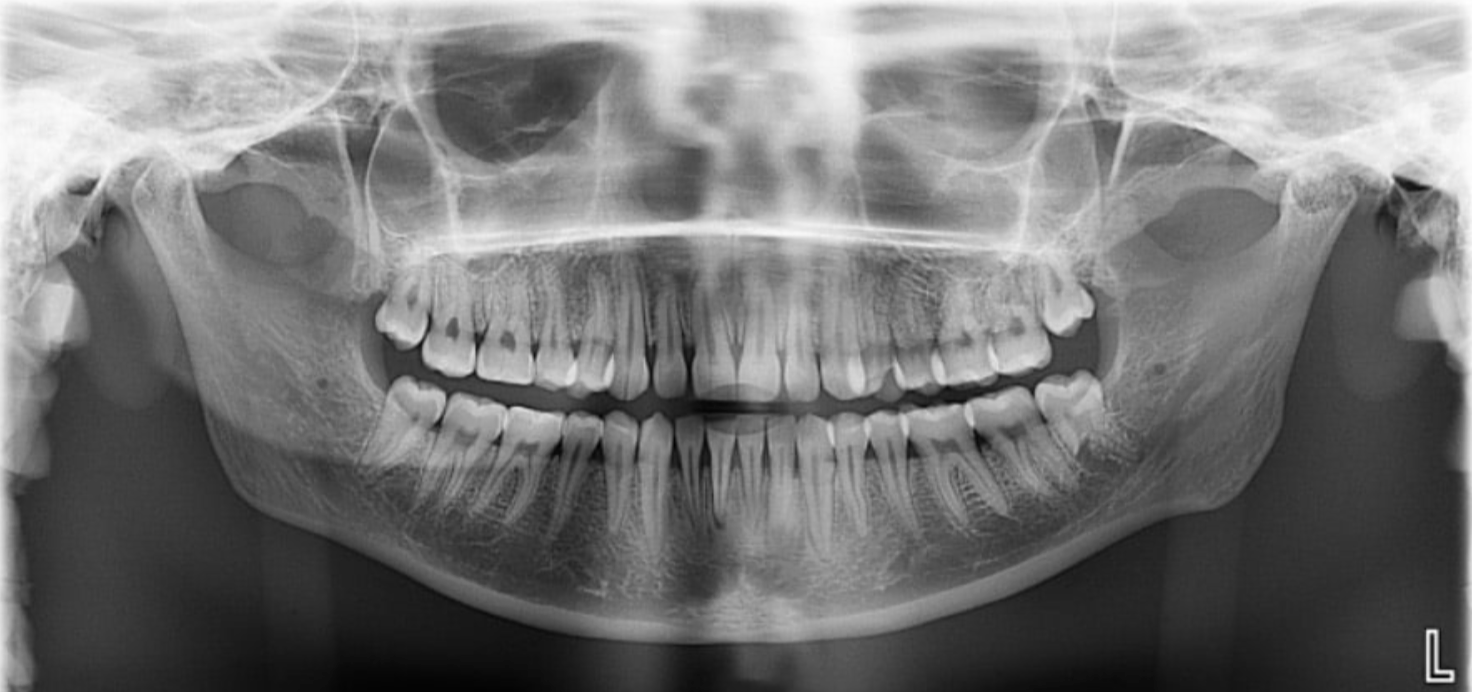

What type of beam is used in a panoramic radiograph?

A vertical beam

What is the focal trough in a panoramic image?

This is the area that we want to see in focus without distortion.

Where is the film located in a panoramic radiograph?

In front of the patient.

Also note the tube is behind the patient

If teeth are seen as narrow in a panoramic image, what is happening?

It means the teeth are too far buccal/forward, and closer to the film

If teeth are seen as wider in a panoramic image, what is happening?

It means the teeth are too far lingual in the focal trough and are closer to the x-ray source.